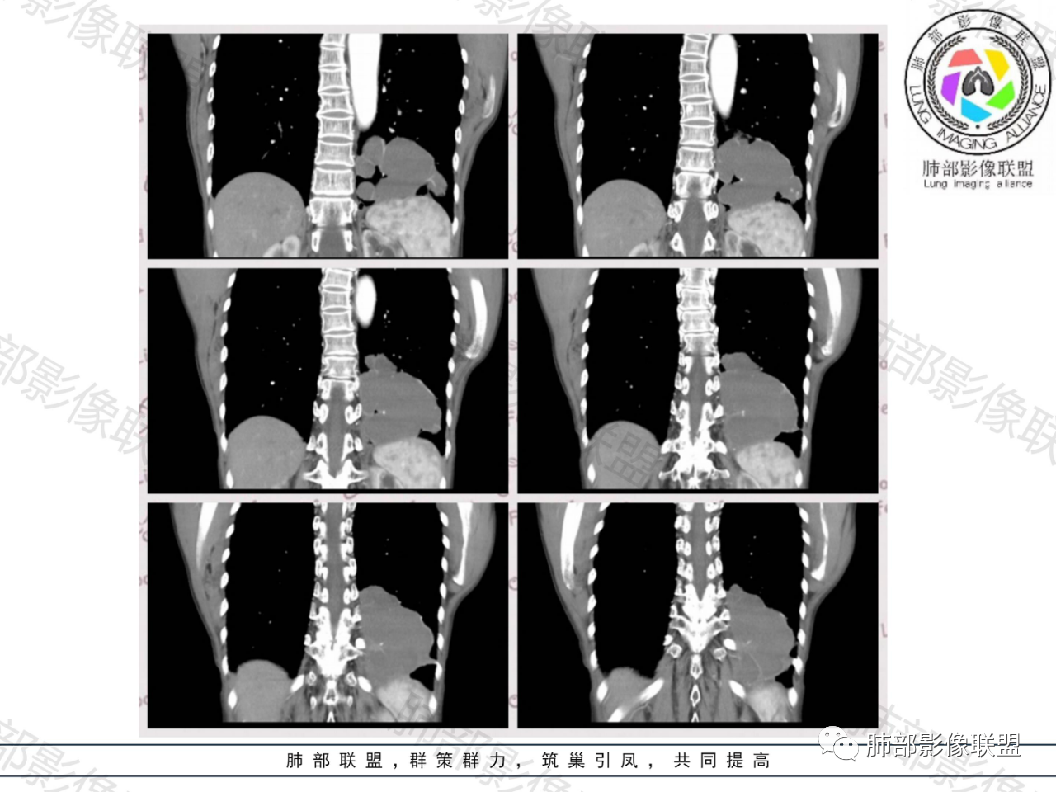

就是一个体循坏的膈下的供血,我为什么考虑先天性的,我觉得左下肺是变小的。

供血:体动脉供血,多来自胸主动脉下部或腹主动脉上部,较为粗大,直径0.5~2cm,异常动脉多在下肺韧带内,经下肺韧带到达病变部位

一、隔离症的血管

1.有体循环供血动脉

2.并无伴行静脉,回流到纵隔的血管不容易见到

3.相应流量的静脉,在隔离症周围通常仅有肺静脉

4.供血动脉形态有改变,常有扩张及退变